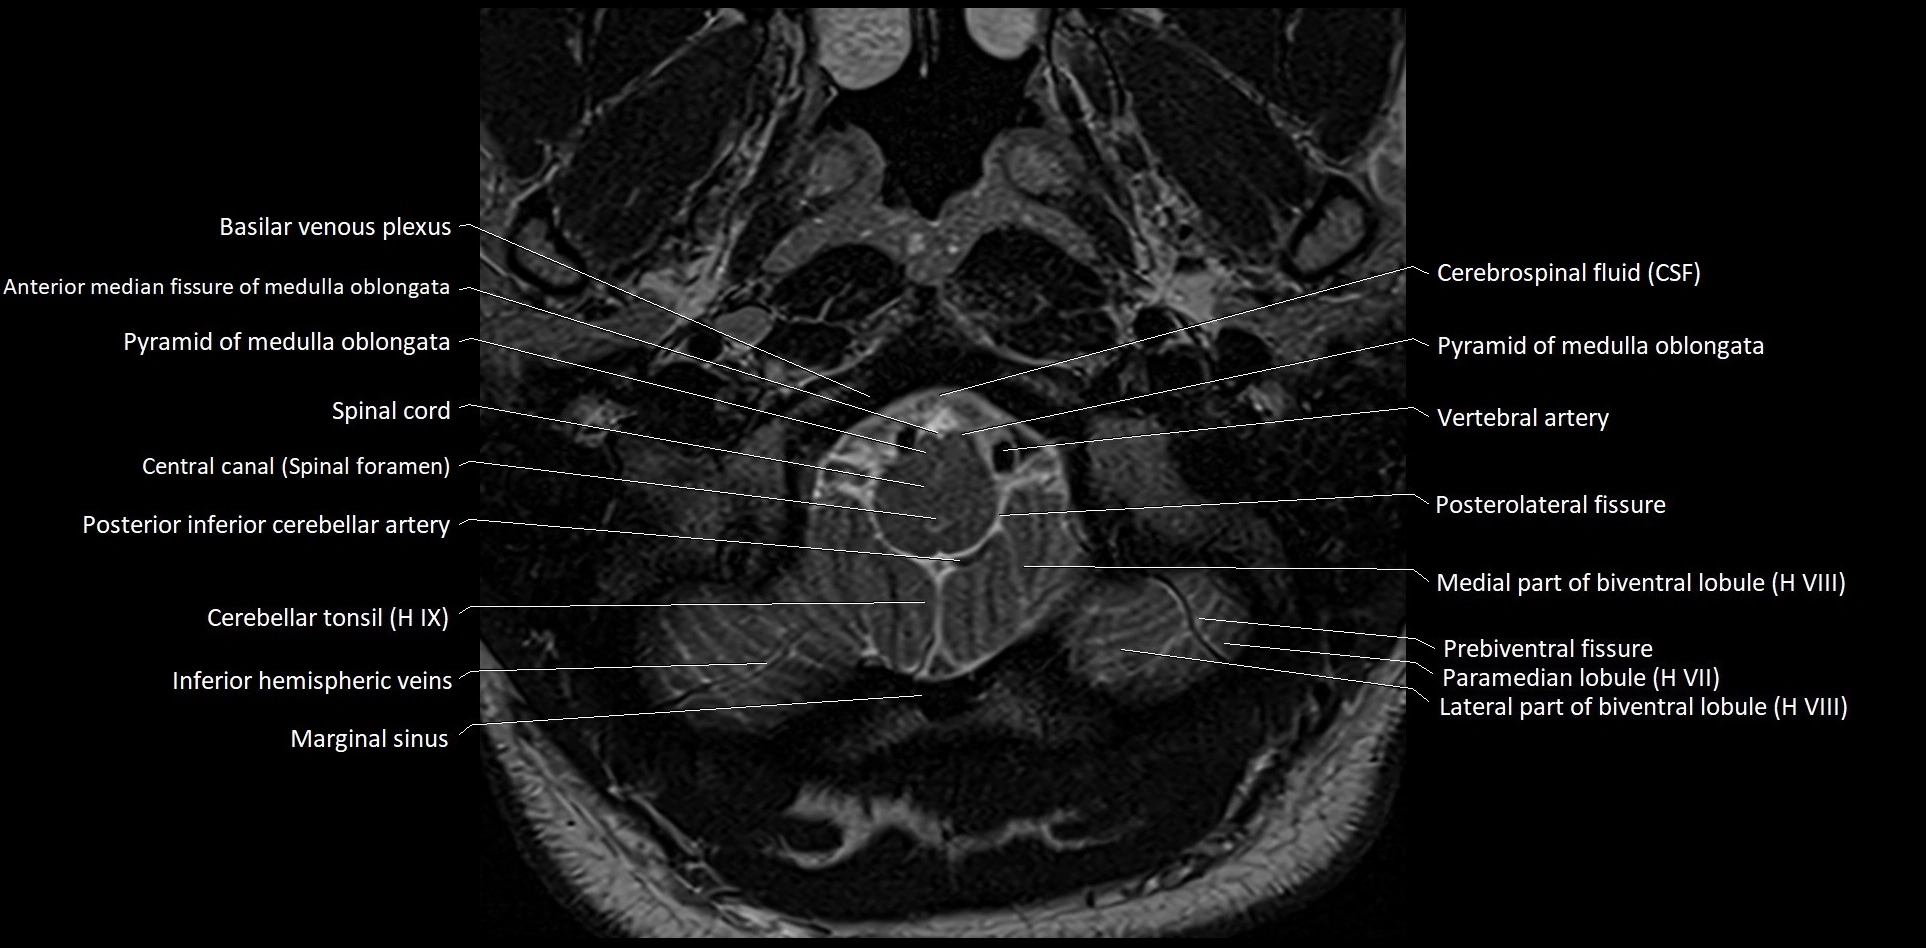

MRI images